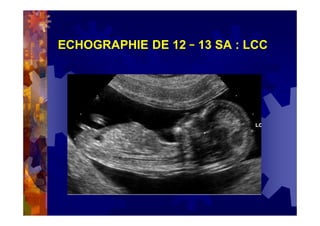

ECHOGRAPHIE DE 12 – 13 SA

= 1ère échographie morphologique

3) Et surtout de mesurer la clarté nucale

= prédictive d’anomalies chromosomiques

(si = ou > à 3 mm? en fonction de la LCC )

en particulier en cas d’ « hygroma colli »

voire d’anasarque

localisation de la grossesse ( GIU / GEU )

vitalité fœtale

nombre de fœtus

datation de la grossesse

chorionicité si grossesse gémellaire

étude morphologique précoce

mesure de la clarté nucale et calcul du risque

d'anomalies chromosomiques

mesure de la fréquence cardiaque

recherche d'une pathologie gynécologique associée